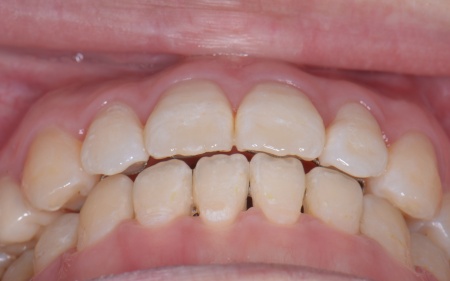

20代女性 歯の根が割れた歯を抜歯したあと矯正治療と骨再生を併用したインプラント治療で補った症例

また、上下の歯を噛み合わせた際に前歯が噛み合わず隙間ができる開咬(かいこう)と呼ばれる噛み合わせも見られました。

開咬は奥歯に負担が集中しやすく、その影響で今回のように歯の根が割れてしまった可能性が高いと考えられます。

以上のことから、抜歯後に歯を補う治療と噛み合わせを改善するための治療が必要と診断しました。

まず、右上と左下の奥歯を抜歯しました。

その後、全体の噛み合わせを改善するため、矯正治療を開始しています。